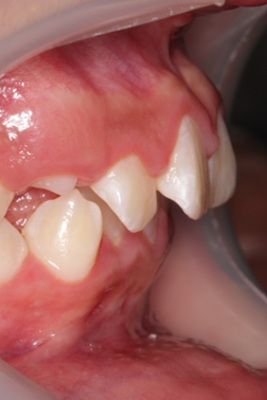

Caso de apiñamiento y sobremordida

Paciente pediátrico, masculino de 9 años de edad, acude acompañado de sus padres debido a la mala alineación de los dientes, y encías inflamadas (gingivitis). Buscan mejorar tanto la estética como la salud bucal desde una etapa temprana.

El paciente en su consulta de diagnóstico

Durante la valoración clínica se identificaron los siguientes hallazgos:

- Apiñamiento dental moderado en ambas arcadas

- Falta espacio para la erupción correcta de caninos superiores

- Sobremordida aumentada

- Encías inflamadas con enrojecimiento generalizado (gingivitis)

- Dentición mixta (presencia de dientes temporales y permanentes)